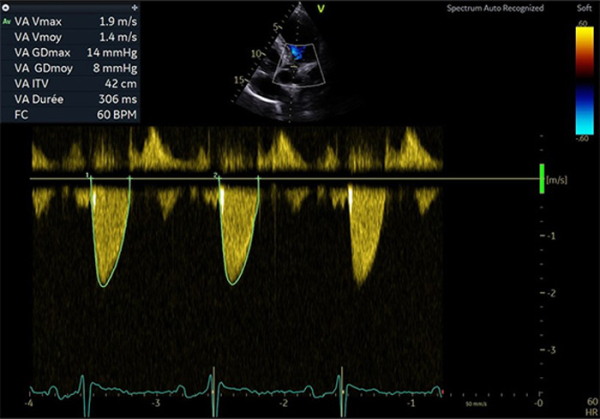

ETT

Figure 2

Vidéo 1

Figure 3

Figure 4

Conclusion de l'ETT :

- CMH asymétrique à prédominance septale (épaisseur maximale 19mm); FEVG préservée et cinétique homogène

- Accélération sous aortique, sans obstruction significative de repos; y compris après Valsalva

- Absence de valvulopathie significative, OG dilatée (56mL/m2); aorte non dilatée

- VD non dilaté, non hypertrophié, de bonne fonction systolique